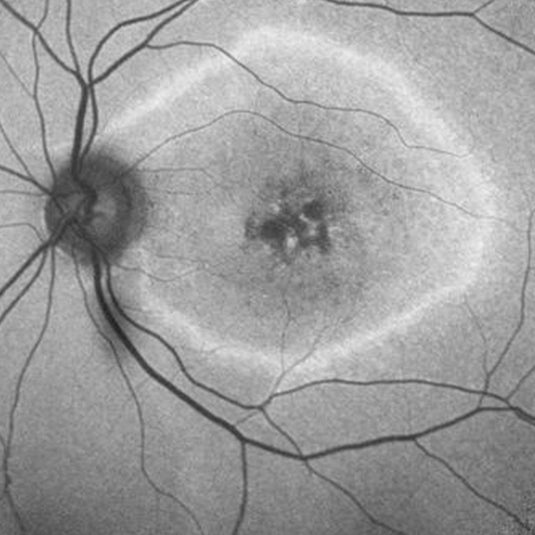

When someone has retinitis pigmentosa, the light sensitive layer in the back of the eye (the retina) begins to degenerate, resulting in slow vision loss. Unlike other more common causes of vision loss, such as refractive issues in the lens (the front of the eye), retinal diseases such as RP cannot be corrected by glasses.